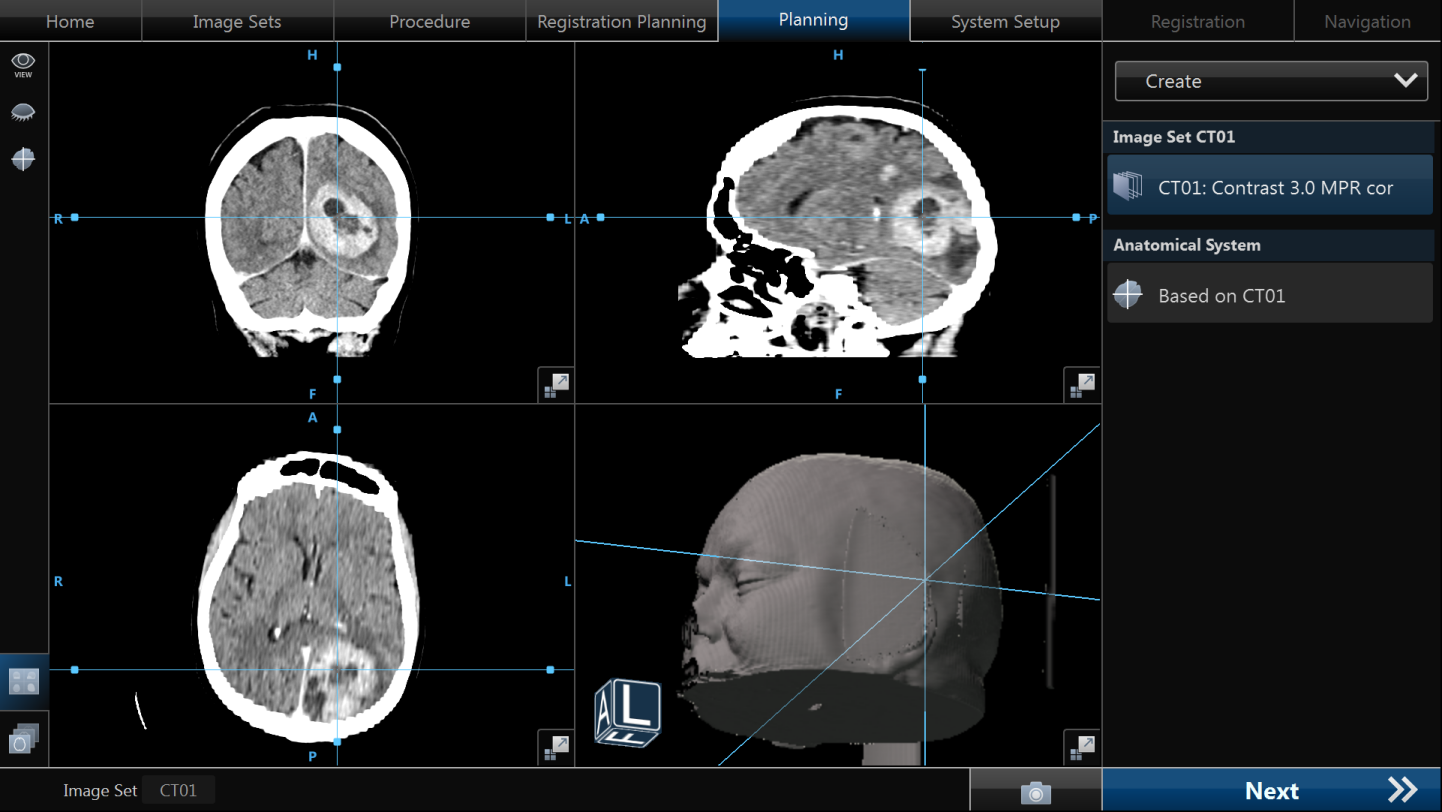

- Tratamentul chirurgical

- Indicat pentru tumorile de mari dimensiuni, la pacienții relativ tineri, cu stare generală bună și încărcare tumorală redusă la nivelul organismului.

- În mod obișnuit se operează metastaze cerebrale unice, dar în cazuri selecționate se pot aborda metastaze cerebrale multiple – chiar și 4 tumori, în același timp anestezic sau în mai multe etape.

- Scopul operației este reducerea încărcării tumorale, obținerea unui diagnostic histopatologic (când nu există deja) și ameliorarea simptomelor prin reducerea edemului cerebral, a efectului de masă și a hipertensiunii intracraniene.

- Un avantaj major al operației îl reprezintă creșterea semnificativă a eficienței radioterapiei, care poate fi efectuată pe volume mai mici și cu doze mai mari.